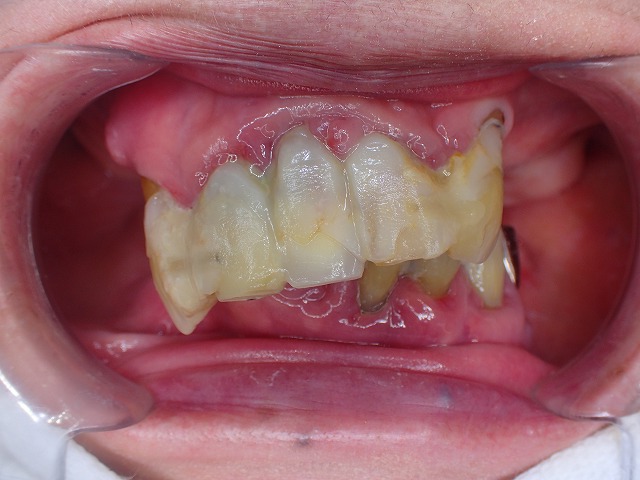

右側の様子

重度歯周病の人は、虫歯も多く

レジン充填などが多いため、

充填を連結することで、固定しています。

左側

今回は、歯が崩壊したので

CAD/CAM冠を制作しました。